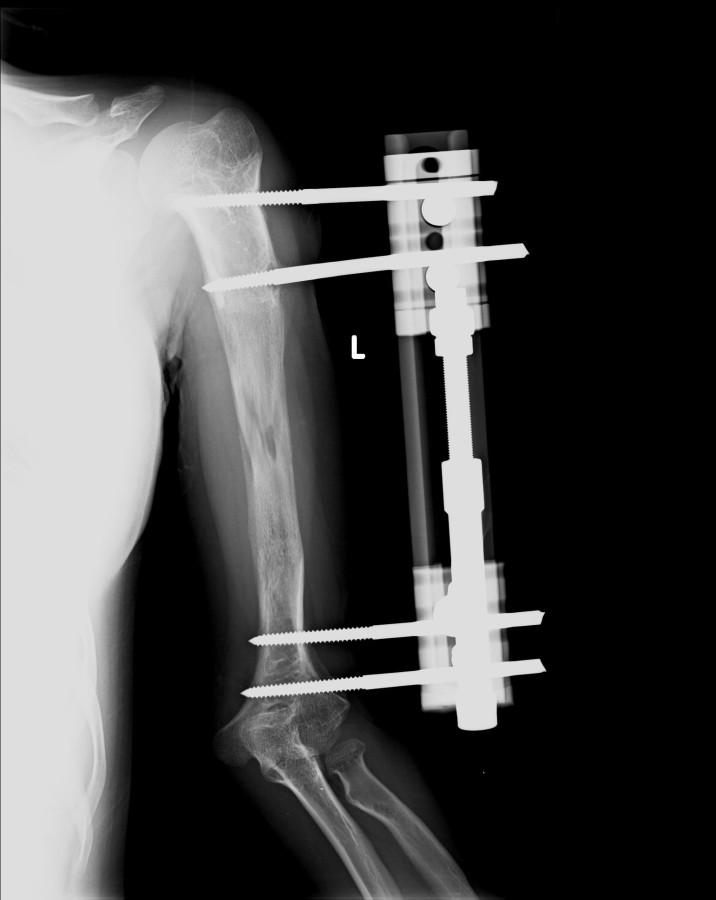

13-15 yaşlar arasında Her iki humerusu (kol) 8-12 cm boy uzatma Dirseklerin fleksiyon deformitesini düzeltme Ortalama eksternal fiksasyon tedavi süresi = 6-8 ay Alt uzuvların iki uzatması arasında üst uzuvlar uzatılarak alt uzuvların dinlenmesi sağlanmış olur. Cihaz çıkartıldıktan sonra en erken ikinci uzatmaya başlama süresi 6 aydır. Bilateral femoral uzatmalarda uzatma fazı sırasında hastanın yürümesi mümkün değildir. Ayakta durmaya sadece hasta transferi sırasında izin verilir. Uzatma fazında ambulasyona sadece tekerlekli sandalye ile izin verilir. Konsolidasyon fazında ise tedrici olarak daha fazla yük verilmesine ve cihazın çıkmasına yakın serbest yürümeye izin verilir. Bilateral tibial uzatmalarda ilk günden itibaren yürüteç veya koltuk değneği ile hastanın yük vermesine izin verilir. Uzun gezintiler tekerlekli sandalye ile yapılmalıdır. Bilateral humeral uzatmalarda hemen hemen hiçbir aktivite kısıtlaması yoktur. Uzatma süresince her iki haftada bir yapılan takiplerde kantitatif duyusal sinir testleri doktor tarafından yapılmalıdır. Bu gelişmekte olan sinir sorunlarını klinik olarak ortaya çıkmadan yakalamaya izin verir. Femoral ve humeral uzatmalarda çok nadir görülmesine rağmen tedavi edilmedikleri durumda düşük ayağa (ayağı yukarı çeken kasları innerve eden sinirin felci) neden olabilirler. Eğer erken tespit edilir ve uzatmanın hızı azaltılırsa, sinir problemi genellikle kendiliğinden düzelir ve uzatmaya düşük hızda devam edilir. Uzatmada yavaşlamaya rağmen sinir problemi devam ederse sinirin cerrahi olarak gevşetilmesi gerekir. Bu işlem 1cm’ lik bir kesi ile yapılabilen ve hastanede bir gece kalmayı gerektiren küçük bir işlemdir. Bu ameliyat el bileğinde sinir sıkışması (karpal tünel sendromu) için yapılana benzerdir.